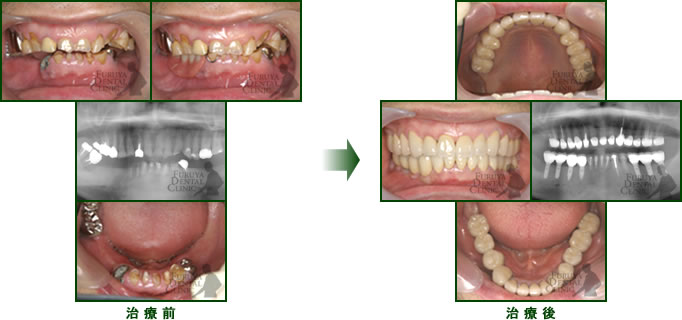

60代 男性

歯牙欠損、虫歯、歯周病の放置による全体的咬合異常。インプラントやセラミック冠で修復。